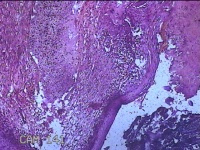

性别

女

年龄

44岁

临床诊断

宫颈赘生物

一般病史

发现宫颈赘生物2年余。

标本名称

宫颈组织

大体所见

灰白暗红色组织3.8x1.5x0.8cm一块,表面光滑,以宫颈12点缝线标记处切开,切面灰白粉红色,质软,宫颈3点处见灰白粉红色囊性肿物1.8x1.5x0.3cm一个,切开肿物,内见大量乳白色内容物,囊壁厚0.1cm。